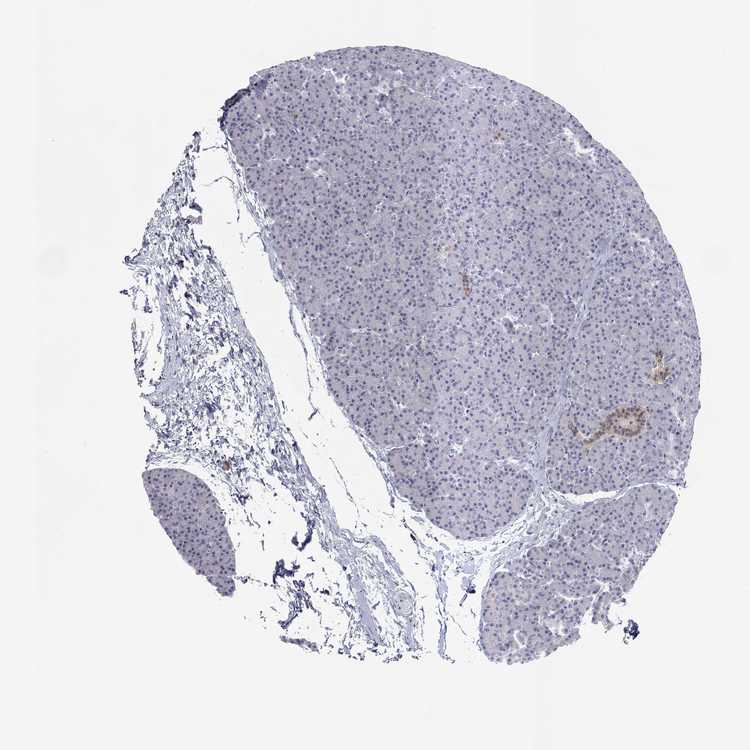

PANCREAS - Antibody stainingi

Antibody staining in the annotated cell types in the current human tissue is reported as not detected, low, medium, or high, based on conventional immunohistochemistry profiling in selected tissues. This score is based on the combination of the staining intensity and fraction of stained cells.

Each image is clickable and will lead to virtual microscopy that enables deeper exploration of all samples and also displays staining intensity scores, fraction scores and subcellular localization as well as patient and tissue information for each sample.

Antibody HPA023099Antibody HPA056734Antibody CAB002138

Exocrine glandular cells Not detectedNot detectedNot detected

Pancreatic endocrine cells MediumNot detectedNot detected